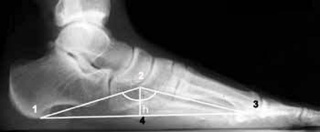

С помощью рентгена можно визуализировать высоту и углы свода стопы, выявить аномалии костной ткани и суставов. Диагностика позволяет выявить наличие деформации и определить степень ее развития.

Выделяют три типа продольного плоскостопия, которые различаются выраженностью симптомов и изменений:

- Первый тип. В начальных стадиях деформации патология слабая, а угол наклона продольного свода стопы колеблется от 130 до 140˚. Визуально определить деформацию невозможно. Пациенты жалуются на симптомы, связанные с чувством усталости после продолжительной ходьбы и периодическими отеками в области стоп. Четкого болевого синдрома нет, есть небольшая болезненность при надавливании на дистальный отдел стопы.

- Второй тип. Деформация выражена умеренно, при испытании угол наклона дуги составляет от 141 до 156 15. Наблюдается видимое уплощение стоп, а при детальном диагнозе — артритные изменения плюсневых костей. Болевой синдром обостряется даже после незначительных физических нагрузок. При этом боль распространяется на всю голень, вплоть до бедра.

- Третий тип. Для этого типа характерно выраженное плоскостопие, когда угол дуги превышает 157˚. Клинические симптомы включают постоянную боль, отек ног, остеоартрит и затруднения движений. Пациенту нельзя носить обычную обувь, и необходимо срочно носить специальную ортопедическую обувь. В запущенных случаях происходит деформация щиколоток.

Обратите внимание, что правильный угол дуги должен составлять 125–130, что указывает на отсутствие деформации.